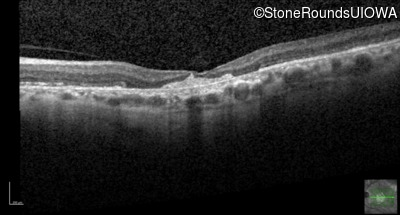

Optical Coherence Tomography - Right - 20/80

Exemplar / OCT Stack

OCT Stack